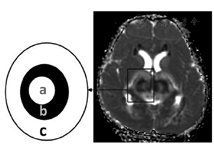

经典ANE神经影像特点(图4)为"同心圆、三色板模式或靶样形状",这种典型改变因为没有T2穿透效应的限制,在头颅MRI的表观弥散系数(ADC)图上尤为明显。病变中央部显示为略高信号,周围病变为低信号(表示细胞毒性水肿),损害灶的外围部有比中央更高的信号(表示血管源性水肿)。ANE的病理改变可解释上诉神经影像学改变。通常,病变的中心是血管周围出血、神经元坏死和神经胶质细胞增生,ADC显示略高信号;在中心的外围部分显示低信号,为动脉、静脉及毛细血管淤血和少突胶质细胞急性水肿;最外层的高信号为病变的渗出,即血管源性水肿。值得注意的是典型的病变主要出现在灰质,特别是在双侧丘脑。

a:丘脑损害灶中央部;b:损害灶中央部周围;c:损害灶的外围部